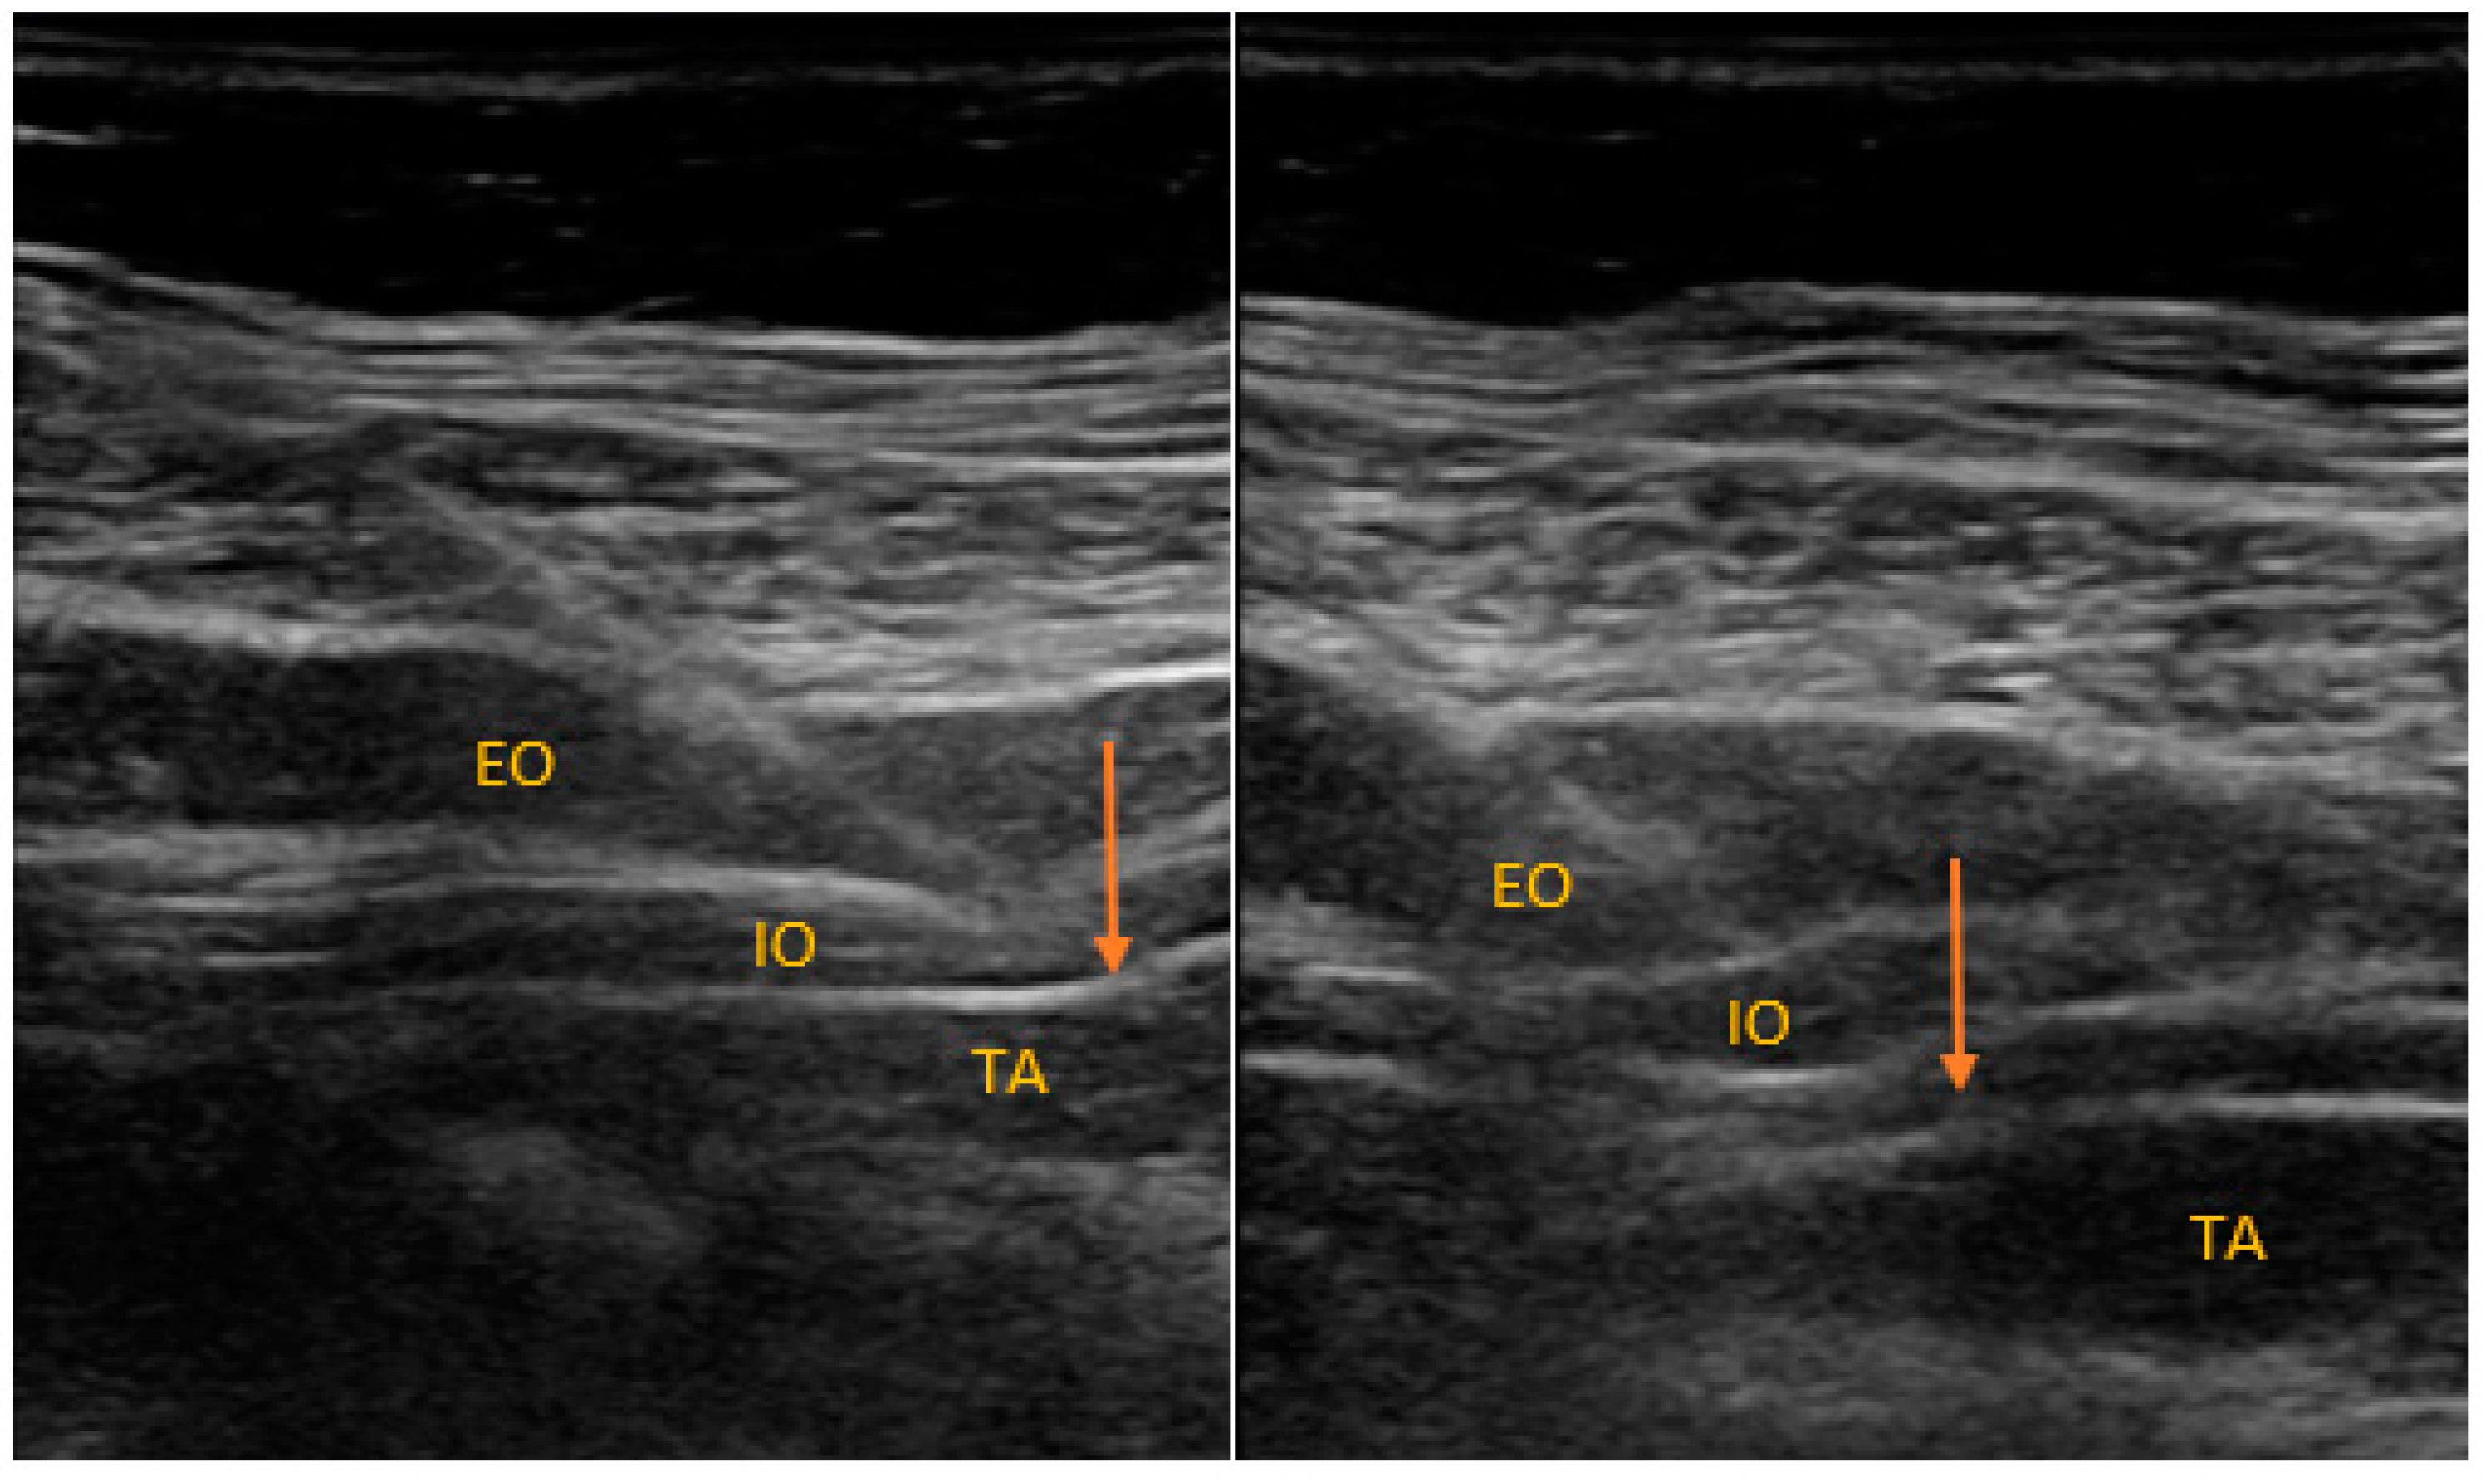

2.2. Anesthesia and Regional Block